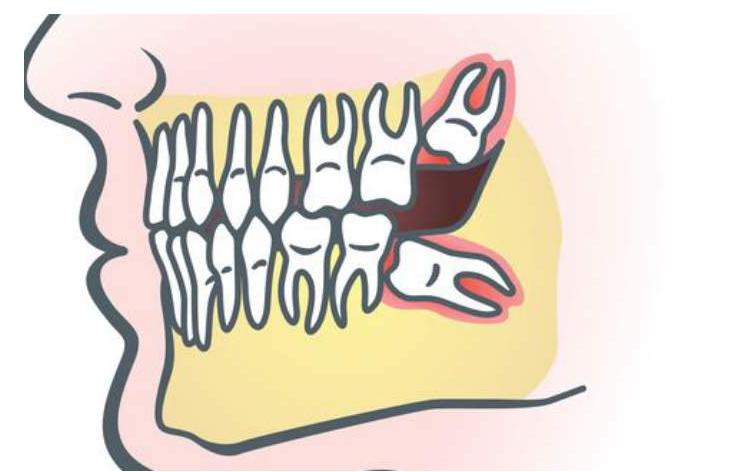

智齿是人类的第三磨牙,由于萌出时间较晚,人类的口腔里已经没有它们的位置,所以它们的生长十分曲折,常常让人疼痛难忍,吃不下饭,夜不能寐,有时还会引发各种炎症。

智齿在萌发的时候,由于人类进化的原因,下颌骨退化,口腔中的位置空间不够智齿生长,导致智齿不能完全萌出亦或是产生阻生牙,从引起牙冠周围组织炎症,这也就是我们常说的冠周炎。

同时智齿生长后,会与牙龈形成盲带,食物残渣得不到有效清洁,时间久了会繁衍细菌,引起冠周炎,轻者,疼痛难忍,吃不下饭,导致睡眠不足,牙龈红肿变成"包子脸"。重者,会使人体的白细胞增加,引发全身症状。